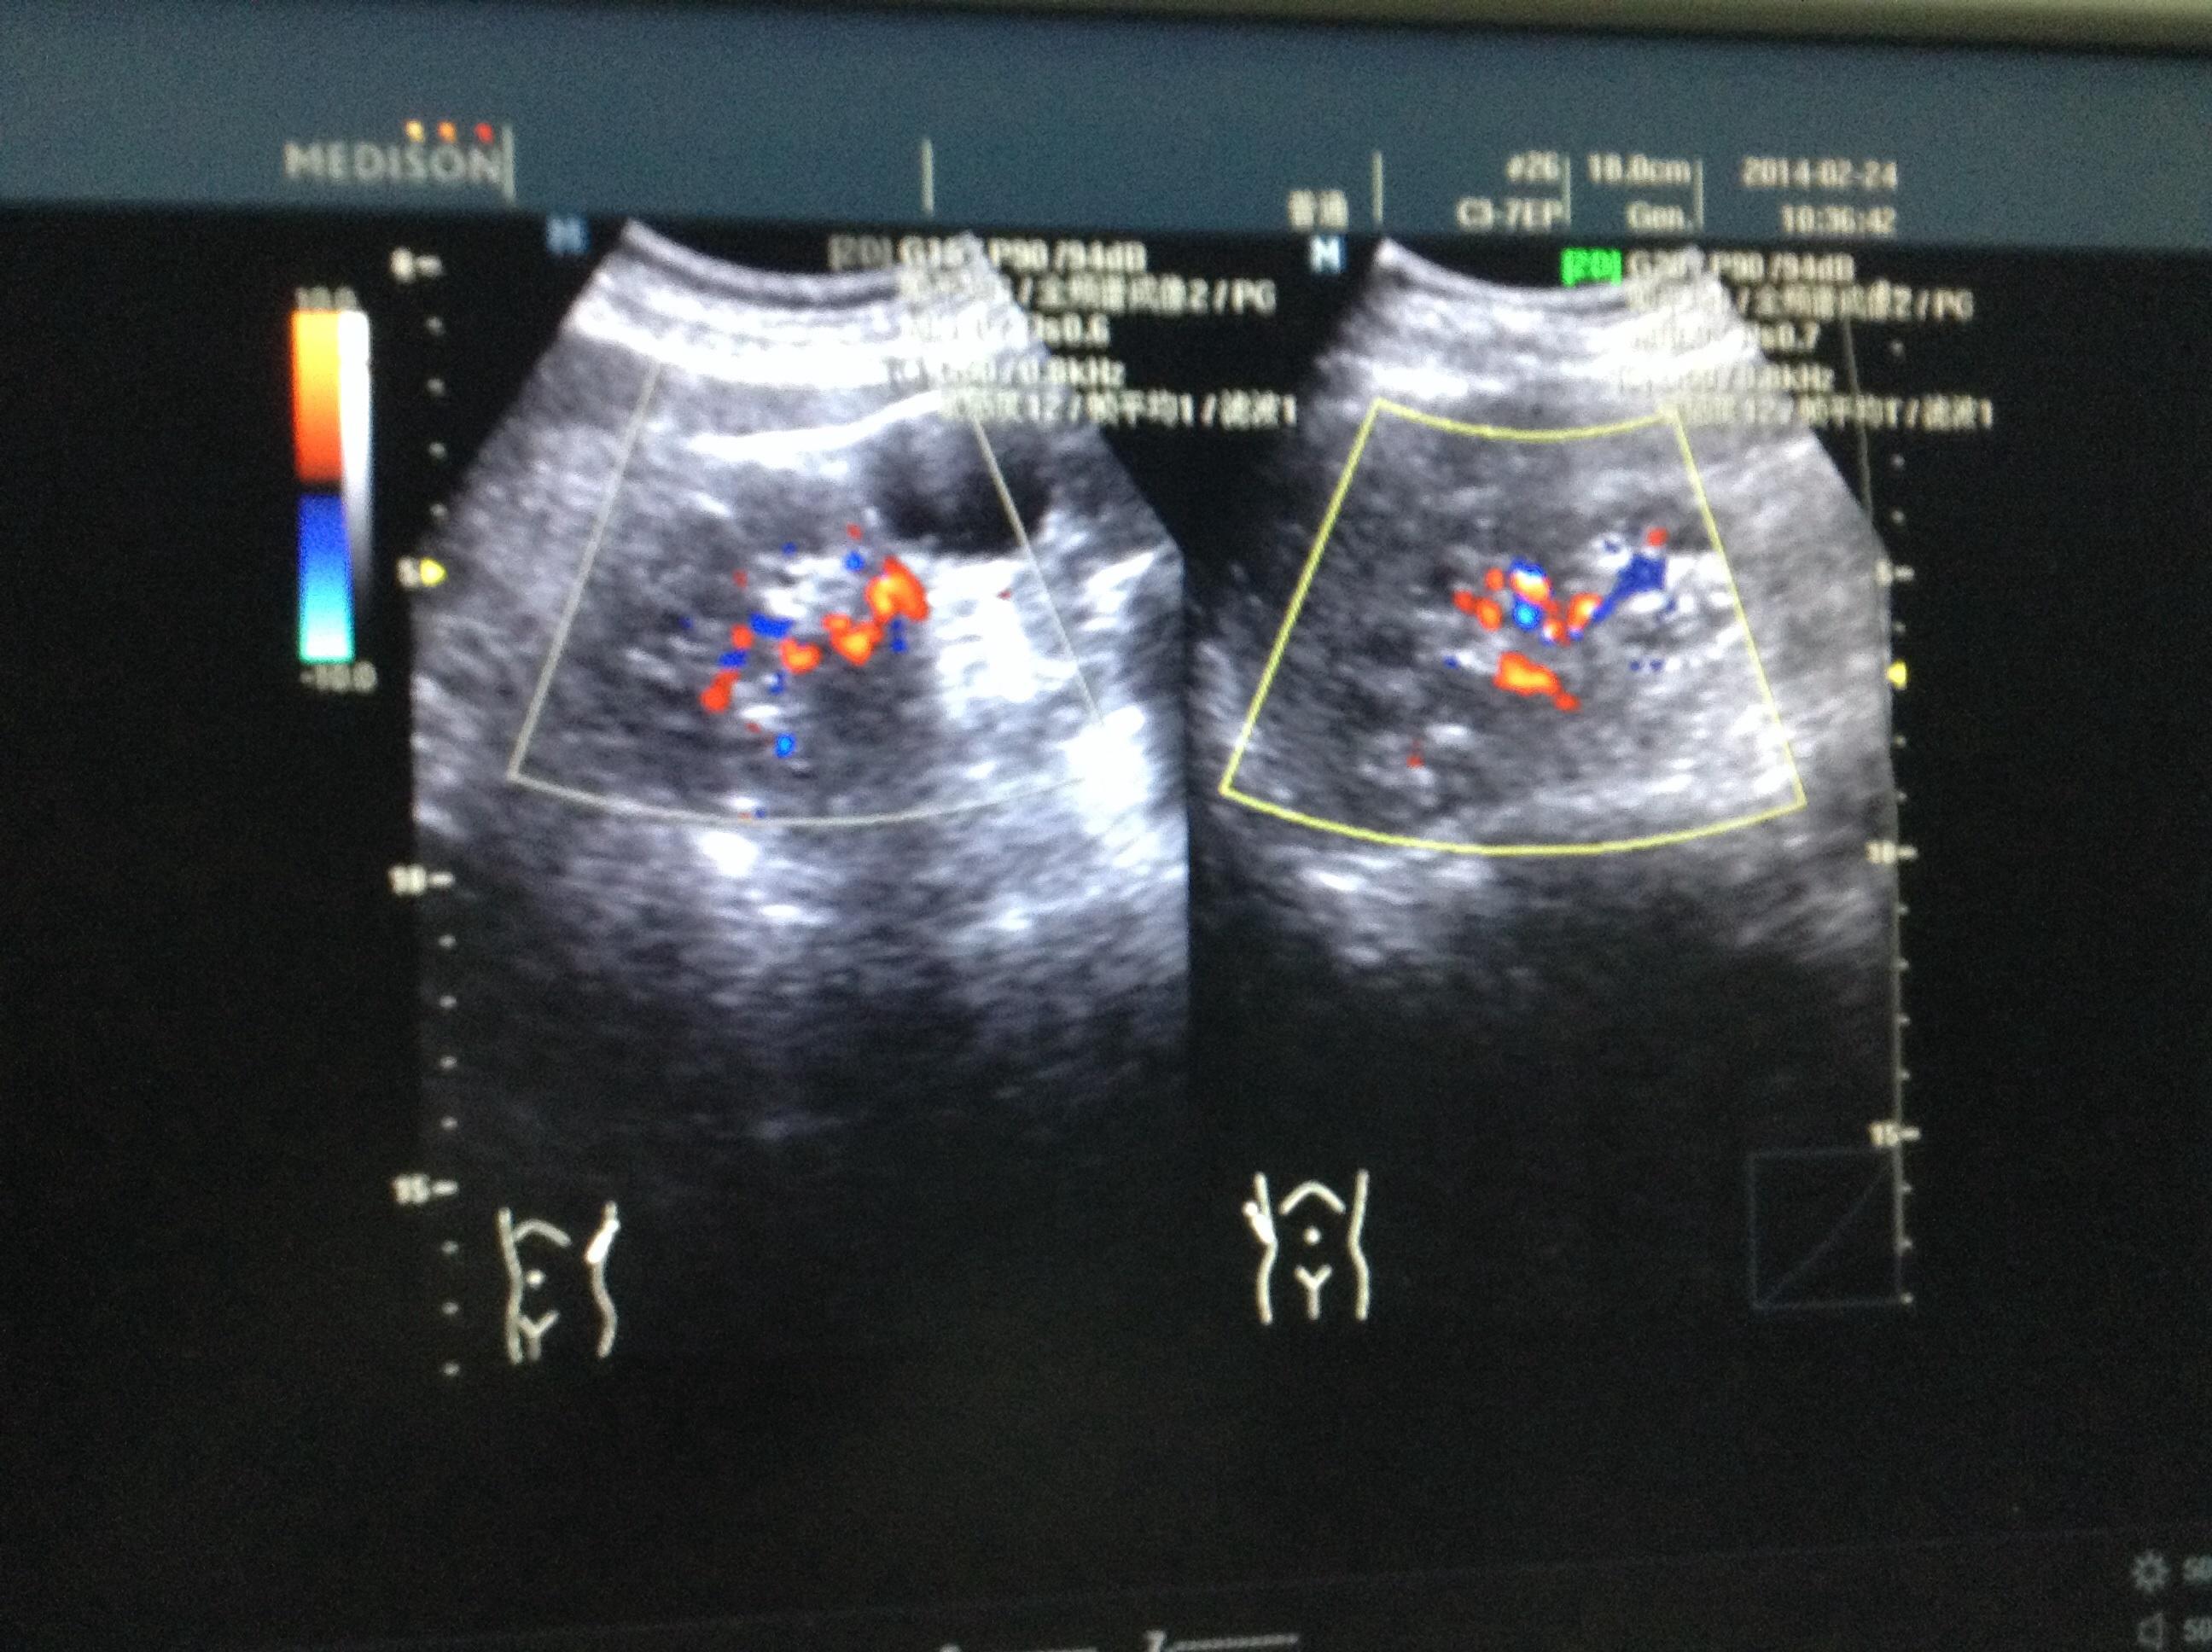

正常肾彩超图

正常肾彩超图,

肾彩超图片